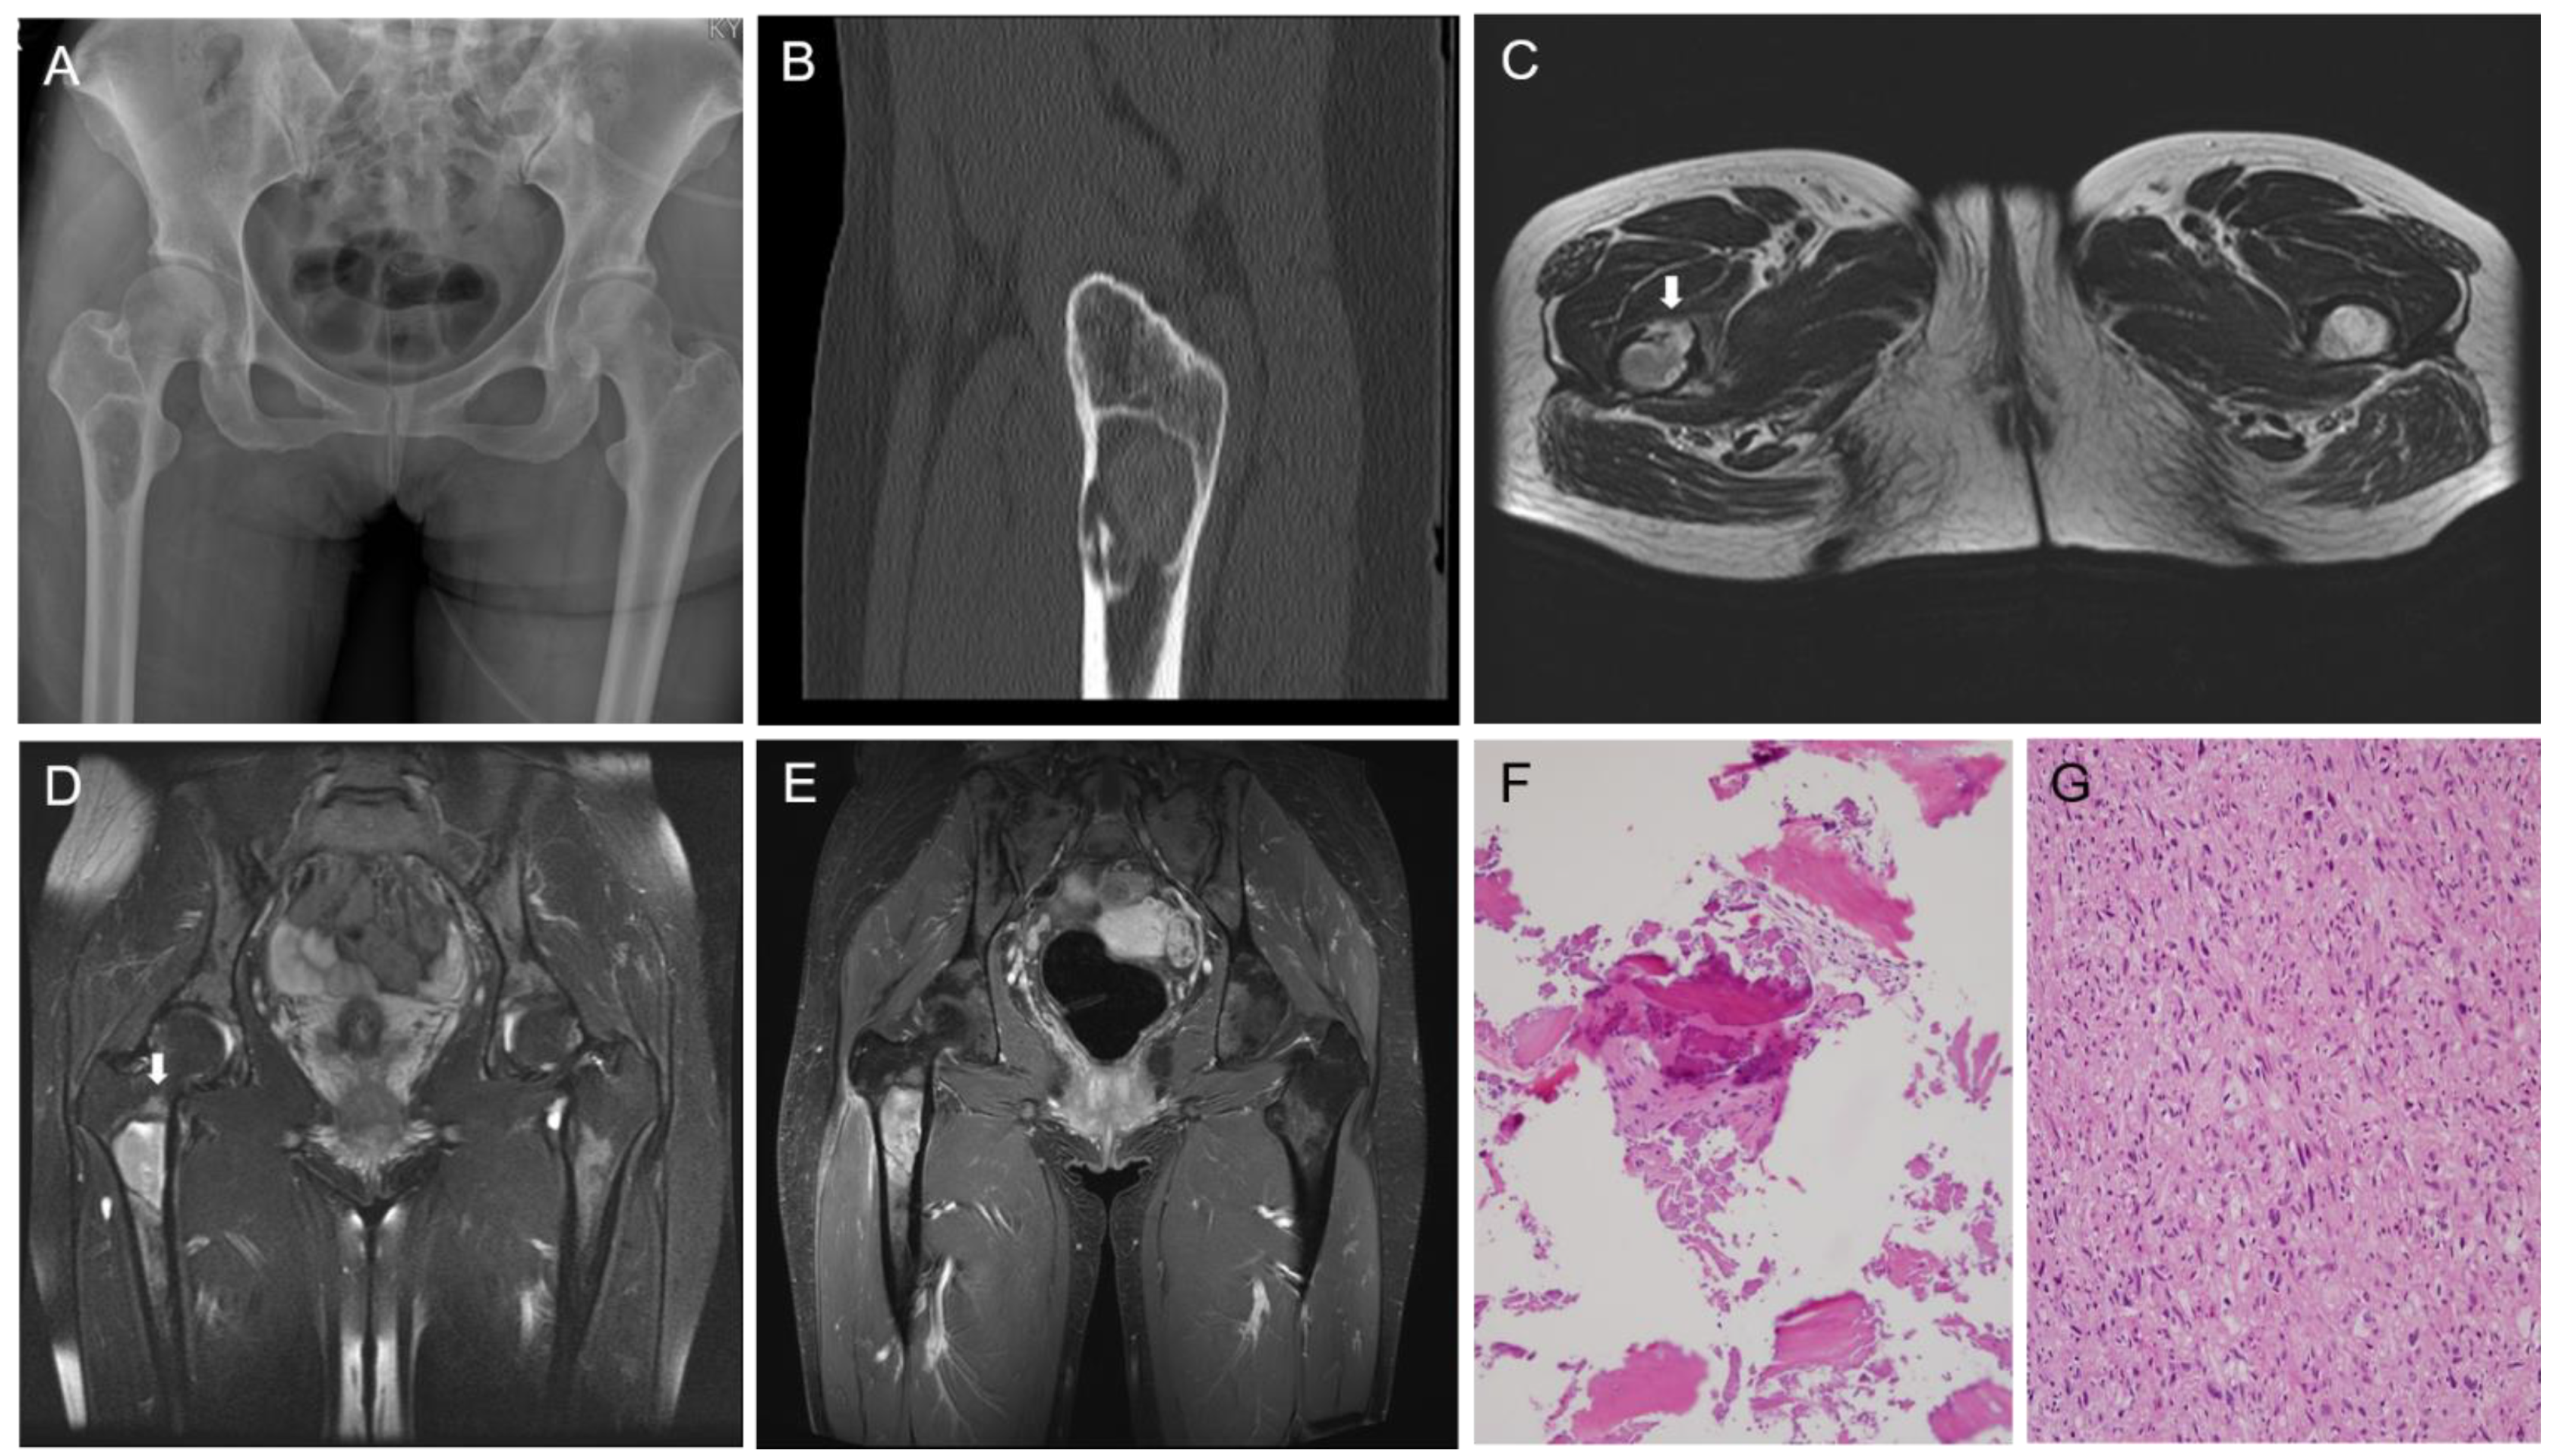

Fibrous dysplasia (FD) is a benign fibro-osseous lesion with varying proportions of fibrous and osseous components. Depending on whether FD affects one or multiple bones, it is divided into monostotic and polyostotic types [1]. The craniofacial bones and femur are commonly involved in monostotic FD [2]. Malignant transformation of FD rarely occurs, and osteosarcoma (OS) is the most common histological subtype [3,4]. To date, there have been few reports demonstrating the molecular profiles of OS in FD [5]. Herein, we describe the clinicopathological, immunohistochemical, and molecular features of OS arising from FD of the proximal femur in a middle-aged woman. A detailed case presentation is presented in Figure 1 and Figure 2. As the degree of nuclear atypia and tumor cellularity in the outer portion suggested high-grade OS, we considered dedifferentiated low-grade central osteosarcoma (LGCOS) and OS arising in FD as the main differential diagnoses. LGCOS can be differentiated from FD by the presence of the following histologic features: infiltrative growth, cellularity, cytologic atypia, and mitotic activity [6,7]. Infiltrative growth, such as permeation or extension to the cortical bone and adjacent soft tissue, is an important gross feature of LGCOS. Microscopically, increased cellularity and intersecting fascicular patterns of spindle cells are usually detected in LGCOS but not in FD. LGCOS shows focal nuclear atypia, including hyperchromatic, enlarged nuclei, and irregular nuclear membranes. In addition to the morphological features, investigation of the underlying molecular profiles is helpful for differential diagnosis. While FD frequently harbors GNAS mutations [8,9], LGCOS frequently shows MDM2 and/or CDK4 amplification [10]. We conducted next-generation sequencing (NGS) analysis to determine whether the high-grade OS was dedifferentiation from LGCOS or malignant transformation from FD. DNA sequence-change analysis revealed GNAS (p.R201H, c.602G > A) and TP53 mutations (p.W53Cfs*70, c.159delG). Copy number variation analysis revealed a gain of PDGFRA, KIT, and CTNND2 and a loss of CDKN2A. TP53 mutations and CDKN2A deletions have been reported in primary OS or secondary OS associated with FD [5,11]. Our NGS results strongly supported the diagnosis of malignant transformation of FD. Following surgical resection and pathological diagnosis, the patient underwent Adriamycin-based chemotherapy and was alive without evidence of disease recurrence for 6 months. This case highlights the macroscopic, microscopic, and molecular characteristics of the malignant transformation of FD into OS. The diagnostic approaches, characteristic images, and interpretations of ancillary tests demonstrated in this case would help pathologists and clinicians make accurate diagnoses of malignant transformation of FD and their differential diagnosis from dedifferentiated LGCOS, which is essential for establishing an optimal treatment plan. A 38-year-old woman with no significant medical history was referred with stabbing pain in right hip joint. The pain occurred during load-bearing activities such as walking for 4 months, and became worse even after taking medicine. (A) X-ray shows a well-defined intramedullary lesion, 5.6 × 3.3 × 2.5 cm in size. (B) CT scan highlighted cortical destruction. (C) T2-weighted axial MR image reveals focal cortical destruction with thinning and endosteal erosion (arrow) in the anterior aspect of the femur. (D) Fat-saturated T2-weighted coronal MR image reveals a well-defined intramedullary lesion with peritumoral bone edema (arrow) in the meta-diaphysis of the femur. (E) Gadolinium-enhanced T1-weighted coronal MR image reveals heterogenous enhancement. (F) CT-guided bone biopsy was performed because pain and radiographic finding of cortical thinning were atypical features for fibrous dysplasia and suggested the possibility of malignancy. The first biopsy specimen includes mainly blood clots with some bland-looking spindle cells and woven bone. (G) The second biopsy reveals atypical spindle cells with moderate-to-high cellularity and frequent mitotic figures.